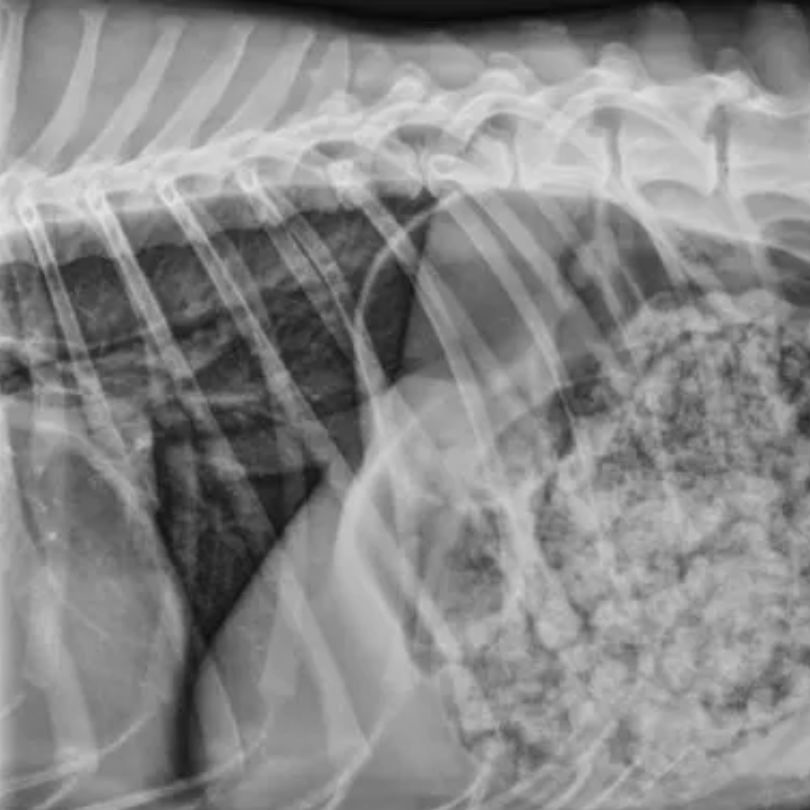

Veterinary radiology uses pet X-rays to evaluate bones, organs, and internal structures. At Aaron Animal Clinic in Parma, radiology helps diagnose conditions such as fractures, bladder stones, and other internal abnormalities.

Many bladder stones, such as struvite and calcium oxalate, are radiopaque and show clearly on X-rays. Others, like ammonium urate stones, may not appear and require additional imaging techniques for detection.